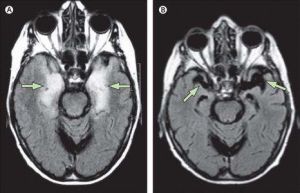

影像學檢查

腦部CT或MRI一般無異常。